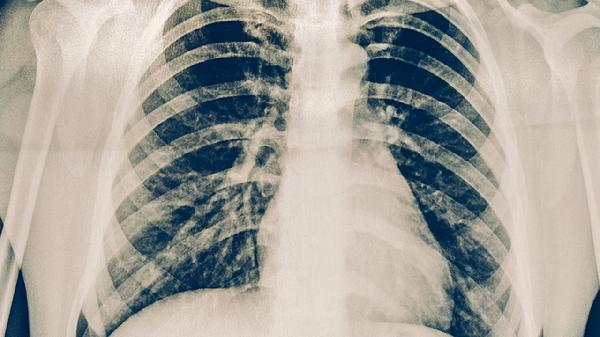

肺结核患者每日应保证1500-2000毫升饮水量,促进药物代谢和毒素排出。饮食需均衡摄入优质蛋白如鸡蛋、鱼肉,配合全谷物和新鲜蔬菜。避免辛辣刺激、油腻食物,戒烟戒酒。保持规律作息,居住环境注意通风换气,遵医嘱完成6-9个月规范治疗,定期复查胸部影像学和痰菌检测。